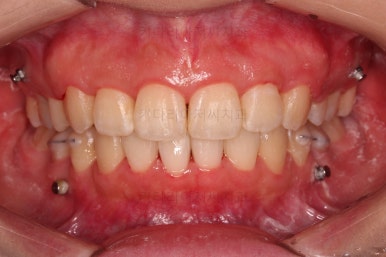

교합, 과개교합 모두 좋아졌고요.

발치 공간도 깔끔하게 닫히고 종료했습니다.

이제 부산무턱교정치과 전후 비교해 볼게요.

웃을 때 튀어나와 보이던 앞니도 많이 개선디ㅗ었고, 치열도 매우 예뻐졌습니다.